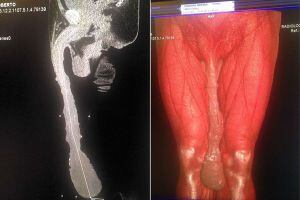

Roberto Esquivel Cabrera es un hombre común y corriente, con la única diferencia de que su pene ha alcanzado casi el medio metro de longitud, todo un récord.

El hombre superó con creces a otro que creía tener el miembro más largo: se trata del actor norteamericano Jonah Falcon, cuyo pene alcanzaba los 24 centímetros flácido y 34 centímetros erecto. El de Cabrera tiene 48 centímetros.